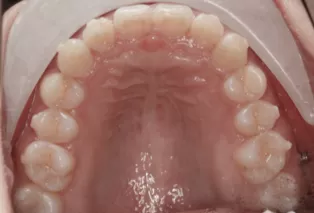

Après traitement

Photos intra-orales après traitement